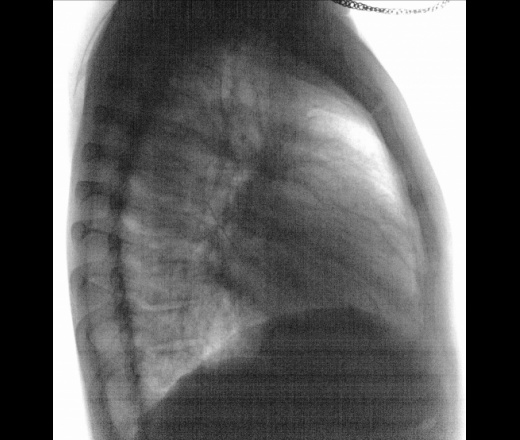

Мужчина 40 лет. Проф. ФЛГ. Увеличение лимфоузлов + очаговые тени с обеих сторон, саркоидоз? От терапевта с диагнозом Z 01.8  для  прохождения диализа. Архива нет.

А жалобы какие? И что за Z 01.8? Не вижу лимфоузлов, а вот сердечко, возможно, стоит проверить

В легких норма

Лимфоаденопатию не вижу, как и очагов.

Сердце митральной конфигурации